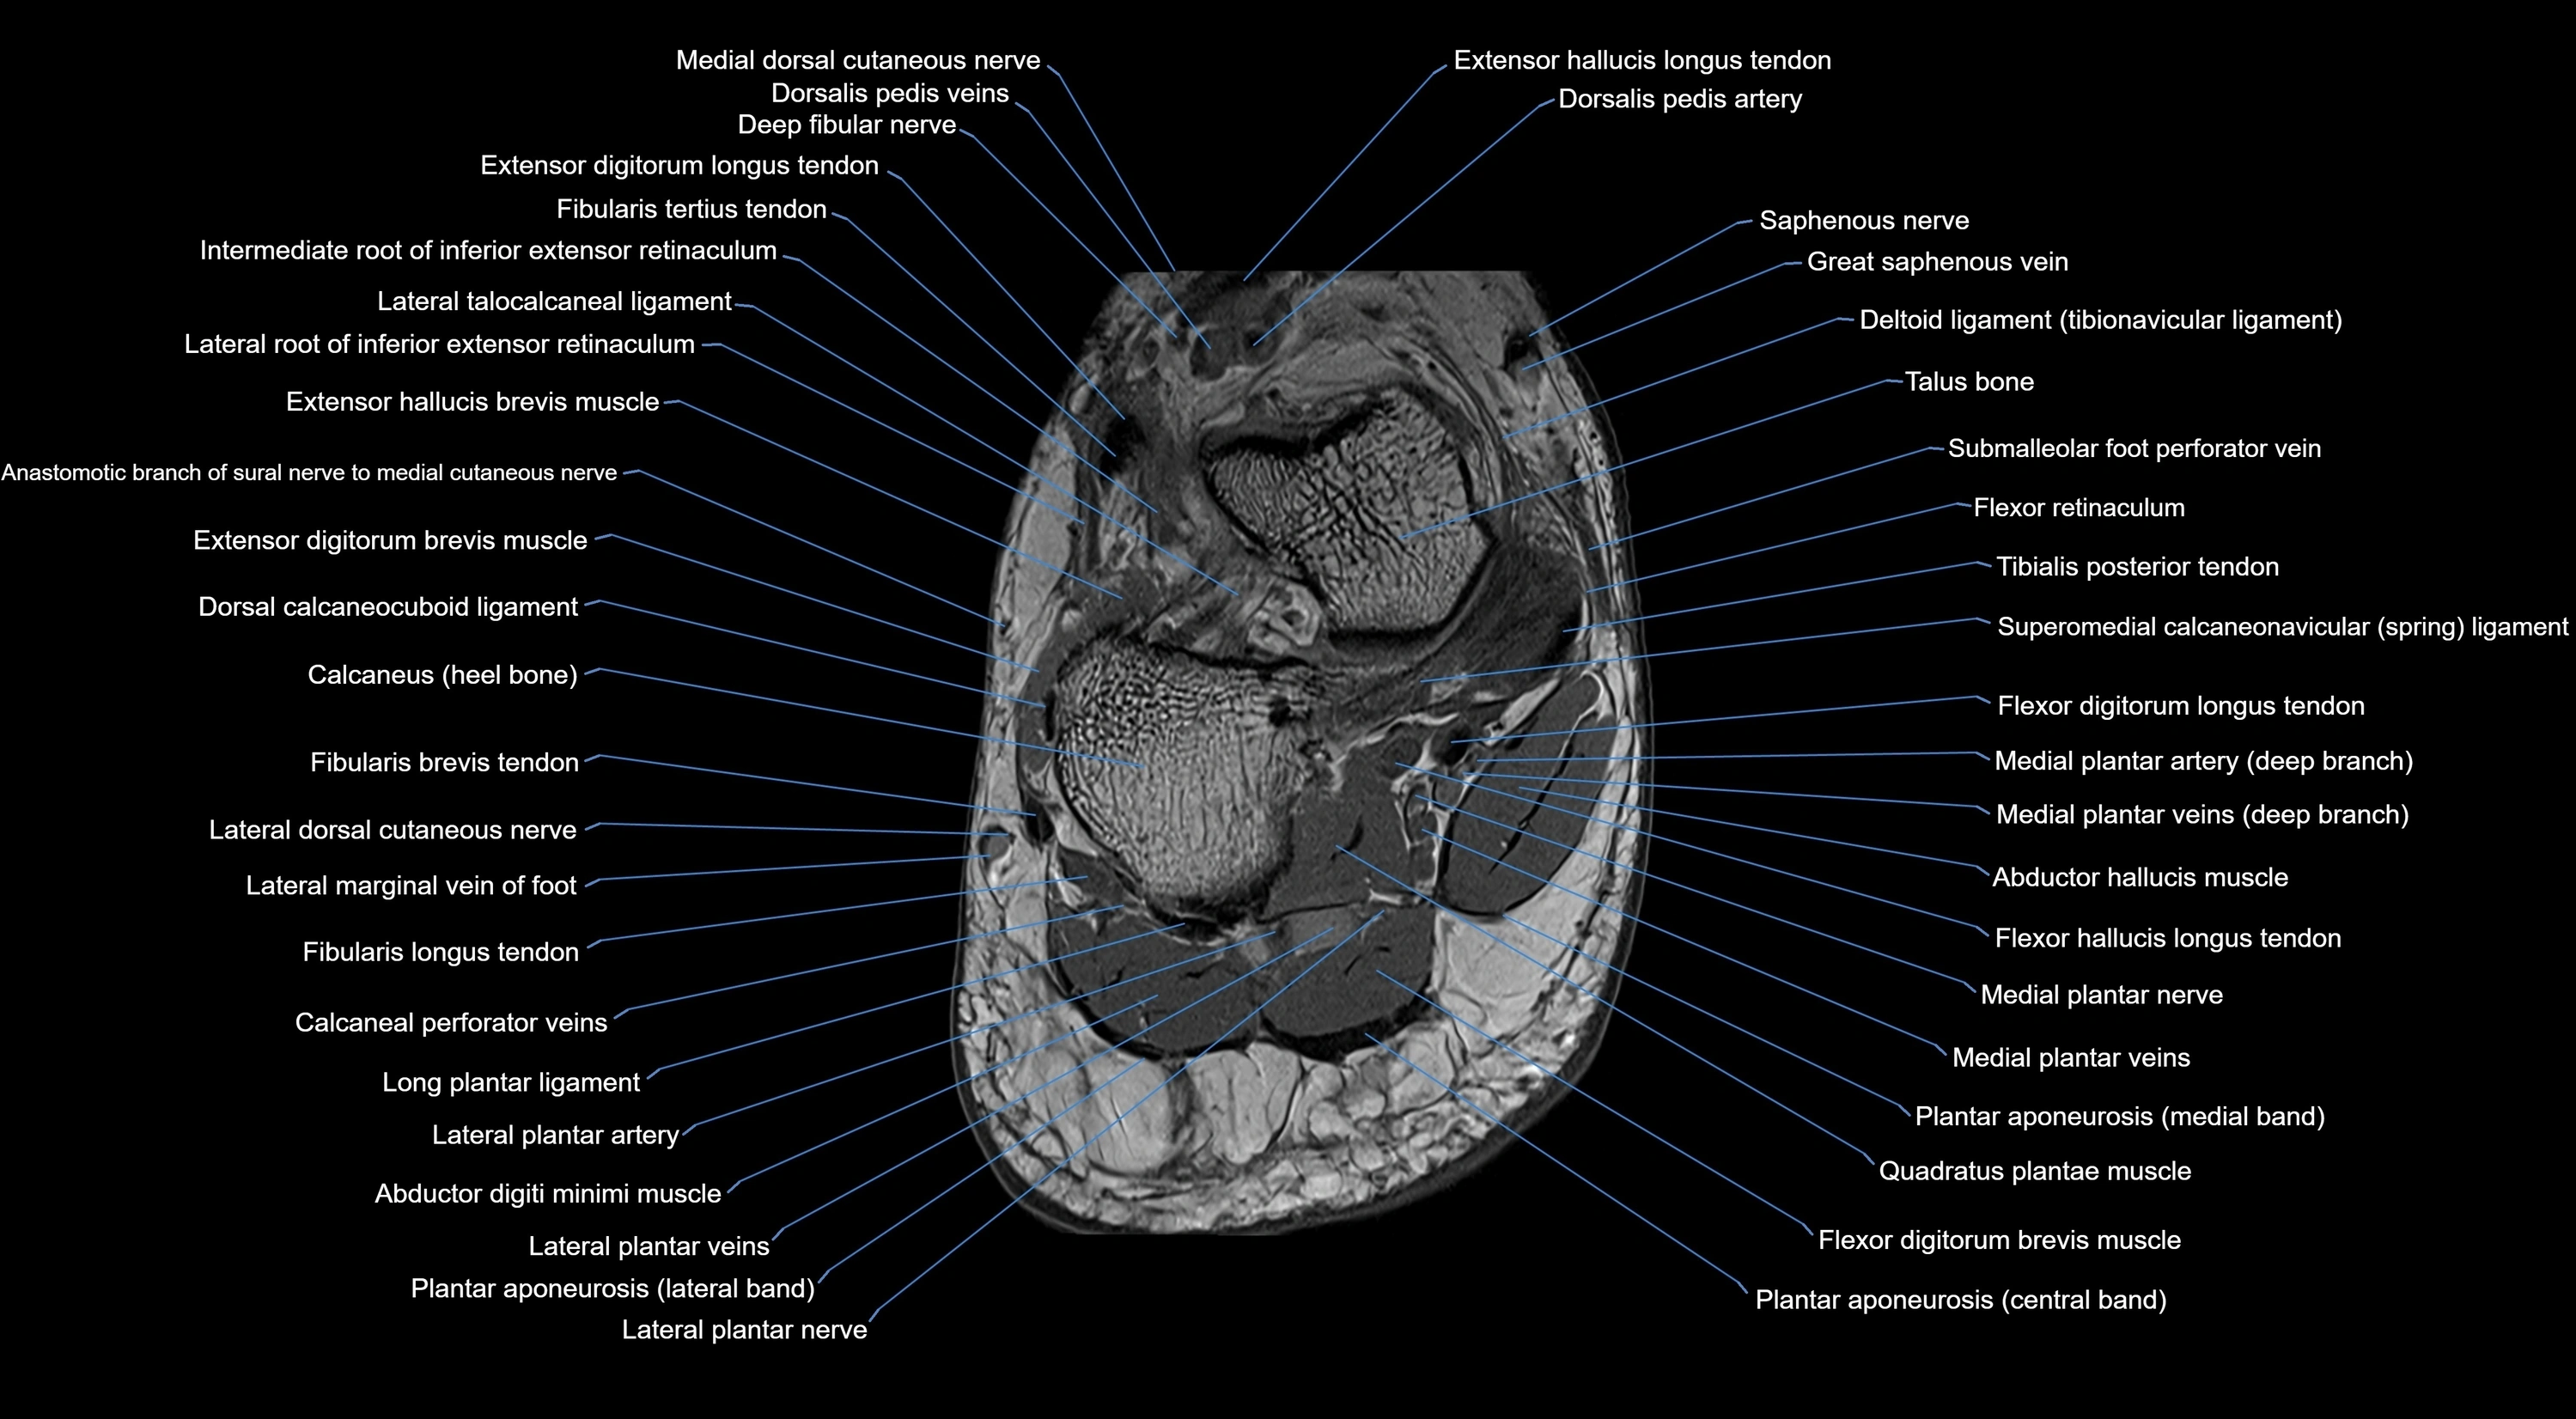

MRI image